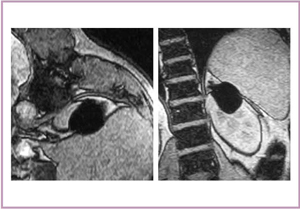

右腎の上局に,早期に造影効果を示す腫瘤が認められ,後期では抜けている(図6)。凍結治療時,MRIでは明瞭な低信号域として氷が描出される(図7)。MRIでは多方向からの撮像が可能で,完全に氷が腫瘍をカバーしているかを確認して治療を進めていくことができる。3週間後の造影CTでは,凍結部位の内部に造影効果が認められる特徴的な所見が得られた。RFの場合は,ほぼ完全に消えてしまうが,凍結治療では造影効果がいつまでも残る場合があり,その評価は今後の課題である。8か月後には,瘢痕組織が収縮していることが確認された。

図7 症例1の凍結治療中のMRI

アイスボールが明瞭な低信号域として描出される。